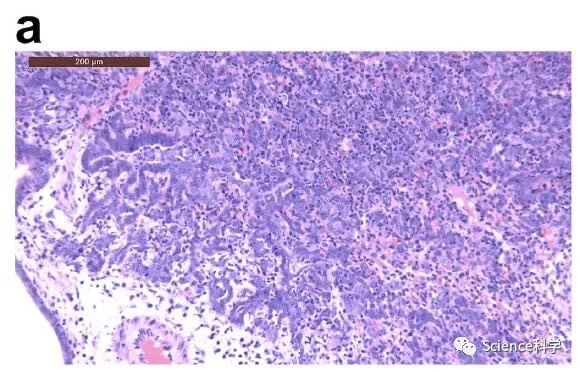

组织病理学检查发现,在接种病毒后2天,有5-10%的肺中炎性细胞增多和实变。

在接种病毒后5天,则有15-35%的肺中炎性细胞增多。